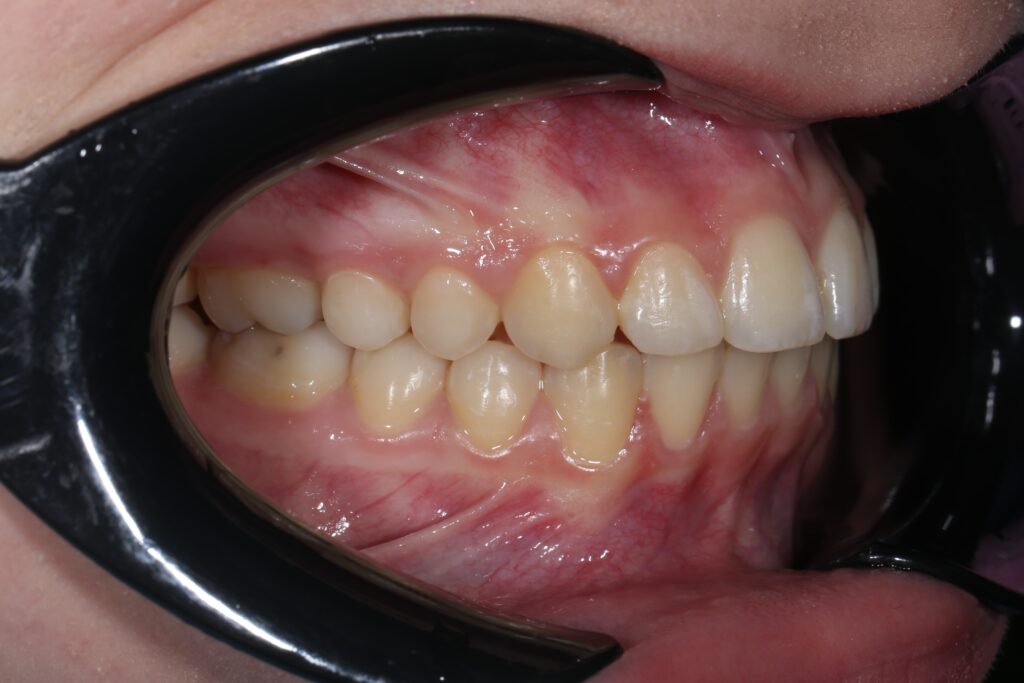

Ситуация до лечения

Диагноз: дистальный прикус, сужение, удлинение верхнего зубного ряда, скученность фронтальной группы зубов на нижней челюсти. Лечение проводилось самолигирующей брекет-системой Damon Q, срок лечения составил 2 года и 2 месяца.

Ситуация до лечения брекетами